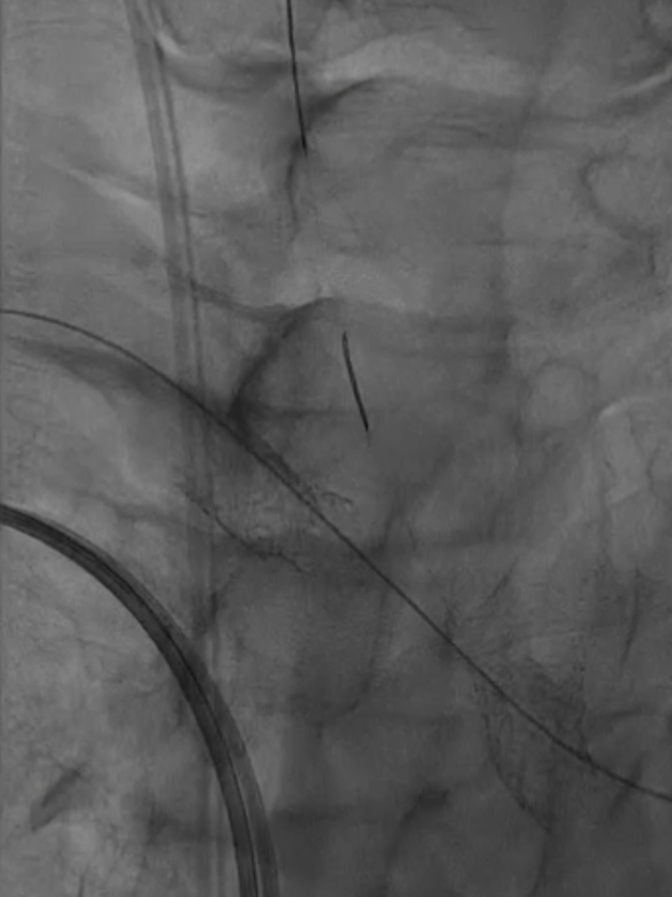

脑保护措施:更换加硬导丝后,采用Filterwire保护伞及0.018导丝选入右颈总动脉,进一步送入右颈内动脉释放保护伞。

跟进长鞘至无名动脉起始

Filterwire 3.5-5.5 保护伞

导丝选入右颈总动脉内

导丝选入右颈内动脉

放置保护伞